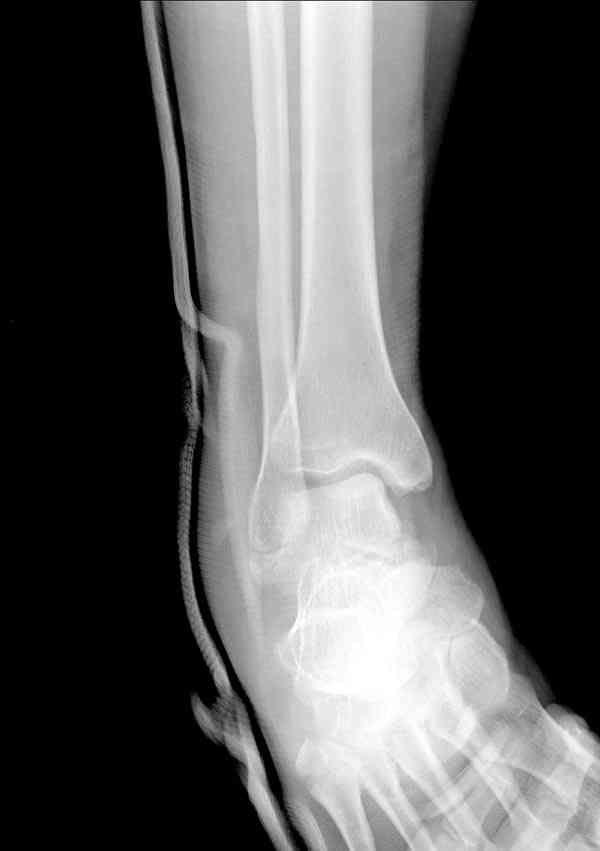

а основании двух видов ренгенограмм невозможно радикально решить о необходимости открытой репозиции или первичного артродеза.

Для оценки состояния нужны дополнительные исследования, например Canale или Broden ренгенограммы и Компьютерная томография.

При переломах тарана всегда имеется риск AVN, а классификация Hawkins поможет разобраться с предполагаемыми осложнениями.

Если в первом типе, когда перелом шейки без смещения, тогда AVN менее 10%, при втором типе когда имеется смещение и вывих тарана в субталарном сочленении меньше 40%, а при типе III когда смещение в голеностопном и субталарном суставах - около 90% и в типе IV, когда происходит полный вывих, риск AVN достигает 100%.

Случай с множественным оскольчатым переломом тарана оперированный из двойного доступа.